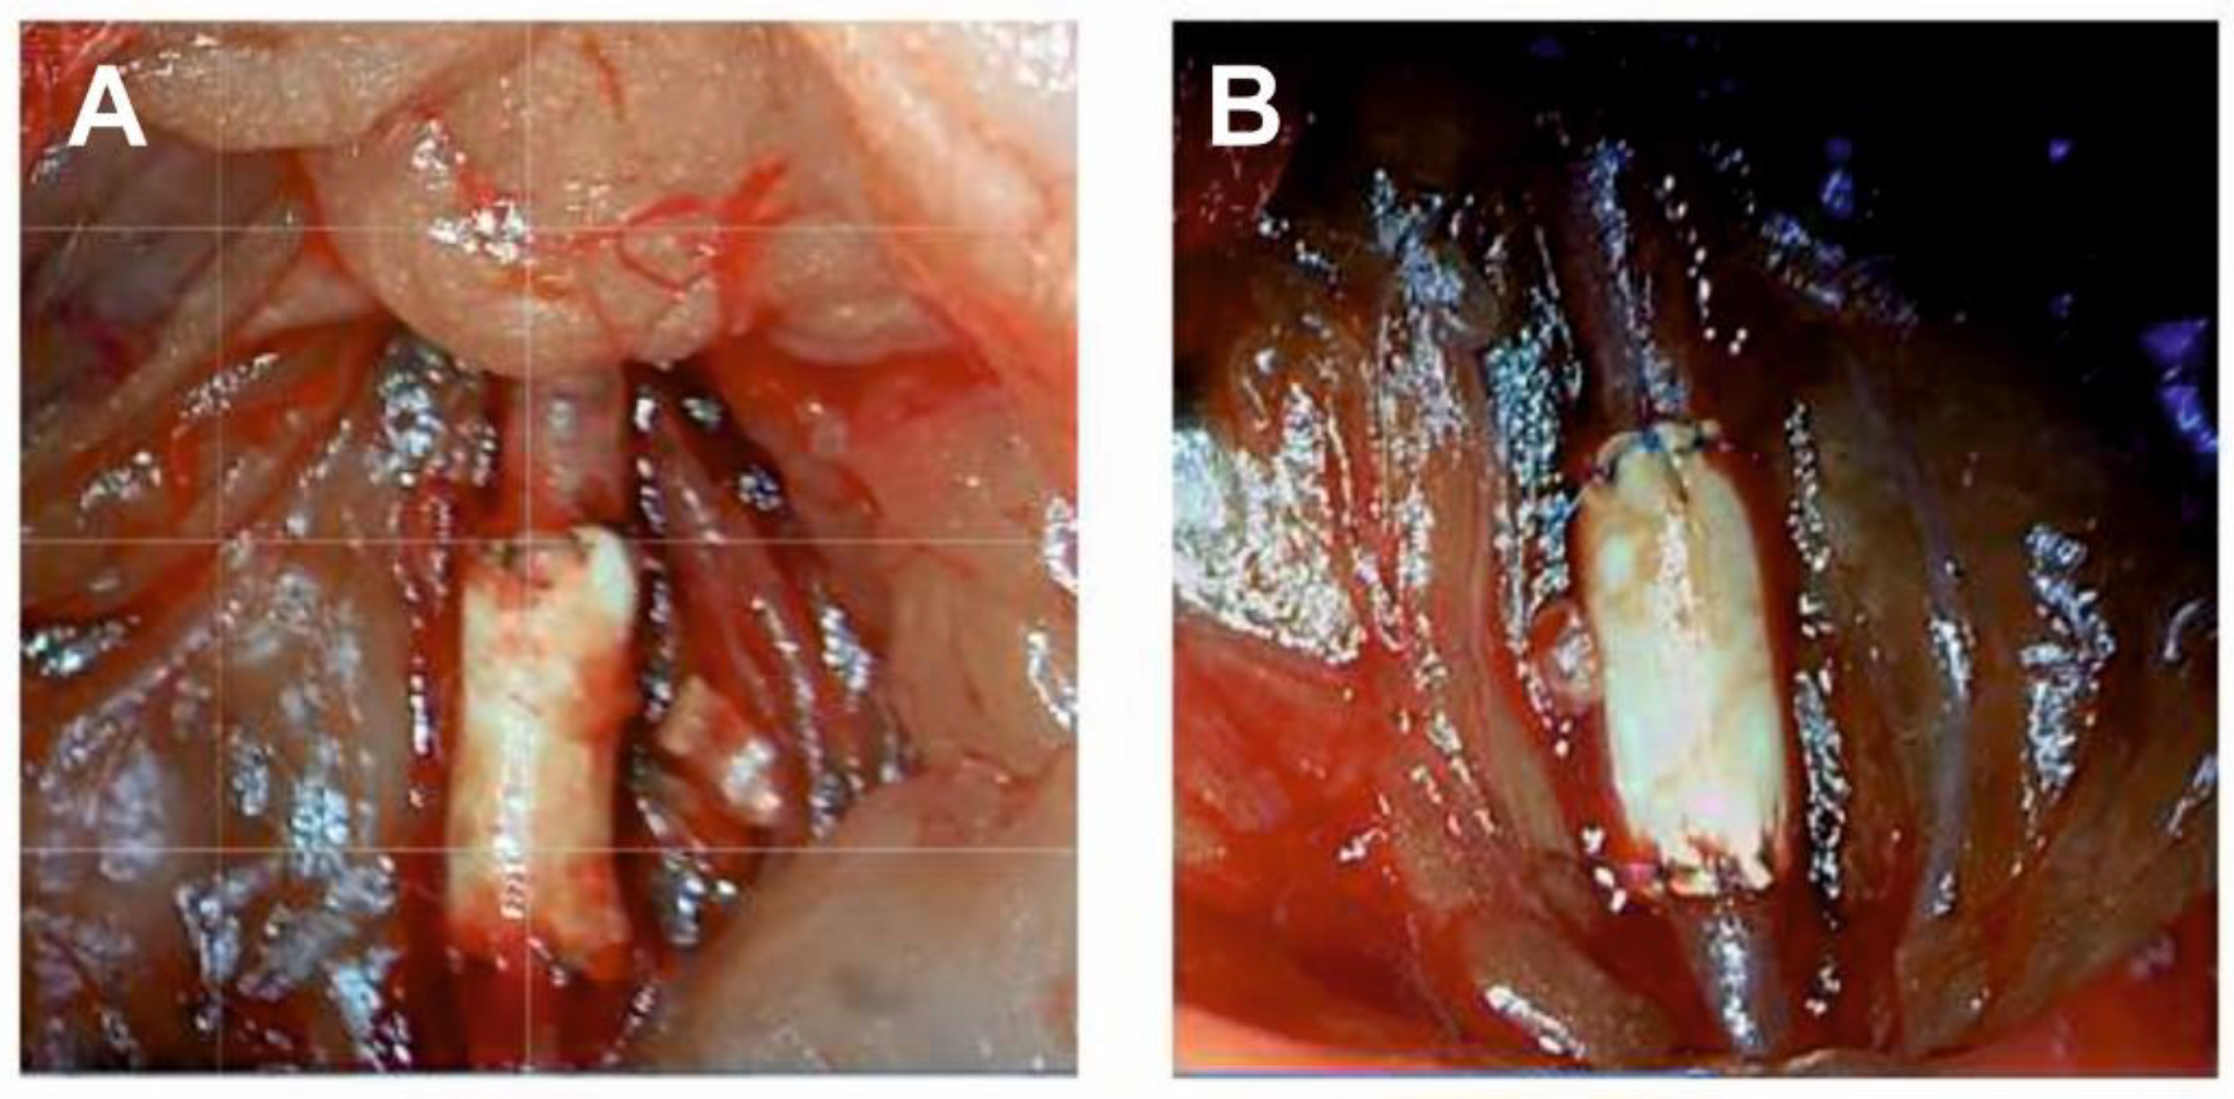

3.3. In Vivo Study of Pel-80A-Based SDVGs